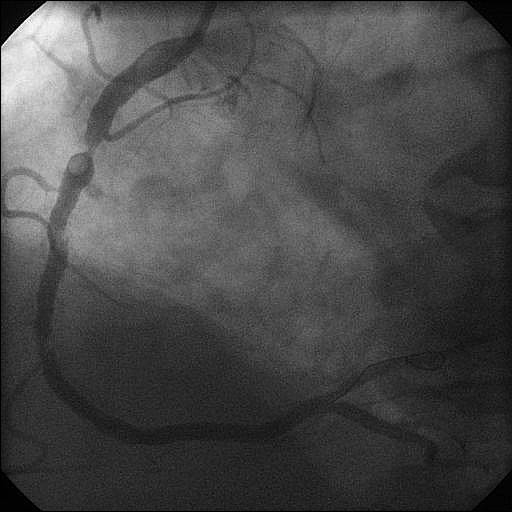

Multiple persisting opacifications of the coronary wall visible in more than one projection surrounding the complete lumen of the coronary artery at the site of the lesion.